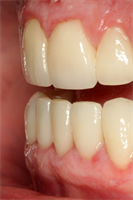

3 Guidelines to Determine When to Use Prosthetic Gingiva!

How do you know when your multi-unit implant restoration will need prosthetic gingiva? This is a challenging situation for many providers but understanding several key concepts should ease your apprehension. 1) Lip position in full smile, 2) presence of existing papilla and 3) the size of...  Read More